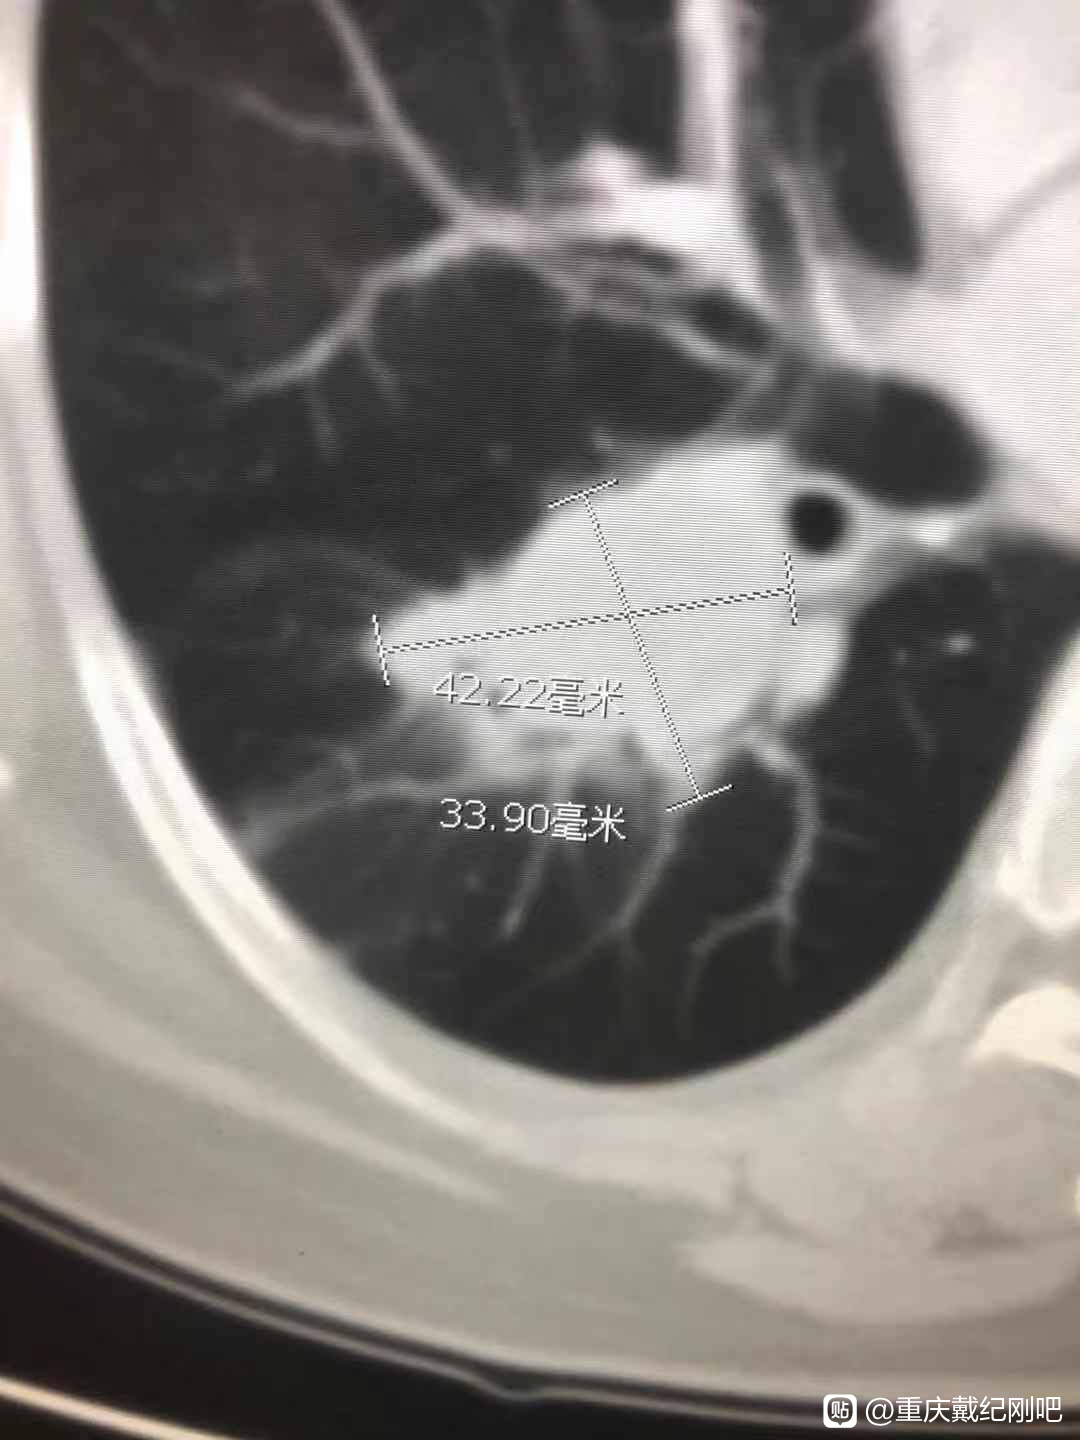

命运真的太不公平了,脑出血的爸爸植物人状态卧床两年多,全家人特别是妈妈24小时不离地照顾了两年多。2020年6月份,妈妈体检做了个CT,医生说妈妈肺上有两个结节,需要做穿刺诊断是恶性还是良性。

结果让我和弟弟真的大吃一惊,妈妈被查出肺腺癌,而且是晚期,不能手术。

基因检测可以做一个,选一个最便宜,3000-4000的基因检测套餐做即可。而且,您母亲这个不一定就是晚期肺癌,很可能是多原发早期肺癌。